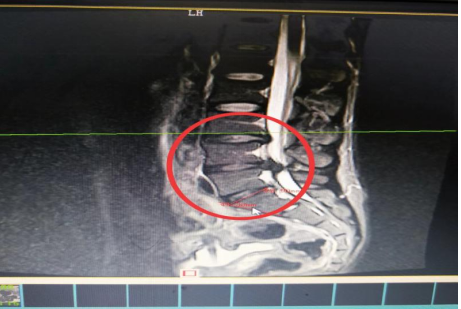

10分鐘后,患者肖先生沒(méi)有家屬陪同的情況下被緊急到骨科一區(qū)病房接診滿頭大汗、非常緊張肖先生,舒小林醫(yī)師仔細(xì)詢問(wèn)了病情。原來(lái)肖先生從事搬運(yùn)行業(yè),半年前就腰腿痛就醫(yī),當(dāng)時(shí)在保守治療后稍有緩解,沒(méi)有引起重視。直到11月13日下午因搬重物后突然感到腰腿劇烈疼痛、麻木、大小便困難這才120急救電話。骨科一區(qū)錢(qián)軍副主任、舒小林醫(yī)師立即給患者作了詳細(xì)的體查,并立即聯(lián)系做急診腰椎磁共振確定有無(wú)神經(jīng)受壓。腰椎磁共振結(jié)果提示:腰4/腰5椎間盤(pán)膨出,導(dǎo)致馬尾神經(jīng)嚴(yán)重受壓,有明顯的手術(shù)指征,如不盡快手術(shù)會(huì)致神經(jīng)受損難以恢復(fù)。錢(qián)軍副主任來(lái)到肖先生病床前,將手術(shù)方案、手術(shù)風(fēng)險(xiǎn)及并發(fā)癥詳細(xì)告知肖先生本人,肖先生表示同意并簽字馬上手術(shù)。

晚上23點(diǎn)肖先生在全麻下行腰椎后路孔鏡下腰4椎板切除、腰4/5脫出髓核摘除、神經(jīng)根管擴(kuò)大成形、神經(jīng)根粘連松解手術(shù)。手術(shù)過(guò)程順利,術(shù)后返回病房時(shí),肖先生下肢便能夠抬腿民。術(shù)后第二天蘇光輝主任錢(qián)軍副主任帶領(lǐng)醫(yī)師團(tuán)隊(duì)查房,肖先生非常開(kāi)心地告訴醫(yī)師“我現(xiàn)在腰不痛了、腳也不麻了,還能自行到床邊上廁所了。感謝,感謝各位醫(yī)師專家妙手回春,感謝護(hù)理團(tuán)隊(duì)的悉心照顧”。連夜趕來(lái)醫(yī)院的媽媽也樂(lè)呵呵地說(shuō):“我代表全家感謝你們!并鄭重地為醫(yī)務(wù)人員一面錦旗。目前肖先生恢復(fù)良好,已于術(shù)后5第五天康復(fù)出院了。